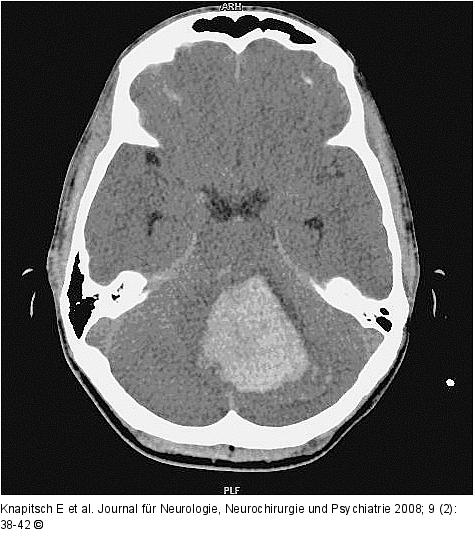

Abbildung 1: FPS Kranielle Computertomographie (CCT): linkscerebelläre Blutung (Durchmesser 5 cm) |

Kranielle Computertomographie (CCT): linkscerebelläre Blutung (Durchmesser 5 cm) |